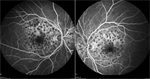

Best-corrected visual acuity measured 20/60 OD and 20/50-1 OS with minimal myopic correction OU. His pupils, intraocular pressure, motility, and visual fields were within normal limits. Ishihara color plates were 4/17 OD and 3/17 OS. Anterior segment exam was notable for early nuclear sclerosis OU. Dilated funduscopic examination revealed bilateral yellow-white pisciform lesions located within the macula and throughout the periphery (Figure 1).

Spectral-domain optical coherence tomography (OCT) showed bilateral subfoveal atrophy with parafoveal ellipsoid layer irregularities (Figure 2). Fluorescein angiography demonstrated hyperfluorescence corresponding to the areas of the retina lesions along with a dark choroid (Figure 3).